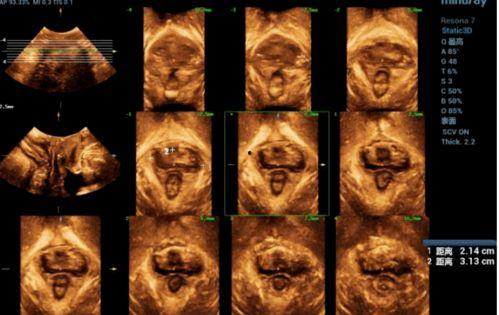

首先,得先了解一下什么是盆底超声检查。简单来说,盆底超声检查是一种无创的检查方法,通过超声波来观察盆腔内的器官,比如子宫、卵巢、输卵管等。而对于女性来说,这种检查尤其重要,因为它可以帮助医生了解盆底肌肉的情况,预防或发现一些妇科疾病。

这时候,神奇的事情发生了!医生会通过屏幕上的视频,向你展示你的盆腔内部结构。哇,是不是觉得有点不可思议?其实,这些视频就像是一幅幅精美的画卷,让你可以直观地看到自己的盆腔内部。

盆底超声检查视频不仅仅是一幅幅美丽的画卷,它更是医生诊断妇科疾病的利器。通过观察视频,医生可以判断你的子宫、卵巢、输卵管等器官是否正常,是否存在囊肿、肌瘤等异常情况。

1. 子宫形态:正常的子宫呈倒置的梨形,如果子宫形态异常,可能意味着存在妇科疾病。

2. 卵巢大小:正常的卵巢大小约为4-5厘米,如果卵巢过大,可能存在囊肿等问题。

3. 输卵管通畅度:正常的输卵管应该是通畅的,如果输卵管不通,可能导致不孕。

4. 盆腔积液:盆腔积液可能是炎症、肿瘤等疾病的信号。